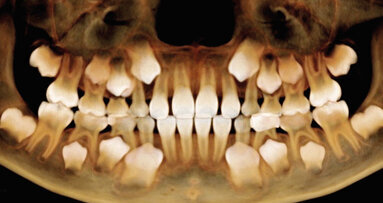

Při preparaci kořenového kanálku často vzniká řada problémů. Mezi ty nejběžnější patří anatomické faktory, které mohou zabránit proniknutí až po apikální zakončení, či vést ke vzniku výstupků, k perforacím a zalomení kořenového nástroje. Zavedení nikltitanových (NiTi) slitin v endodoncii představovalo podstatné zlepšení možností v rámci technik čištění a tvarování kořenových kanálků a současné zkrácení doby ošetření a minimalizaci iatrogenních chyb.